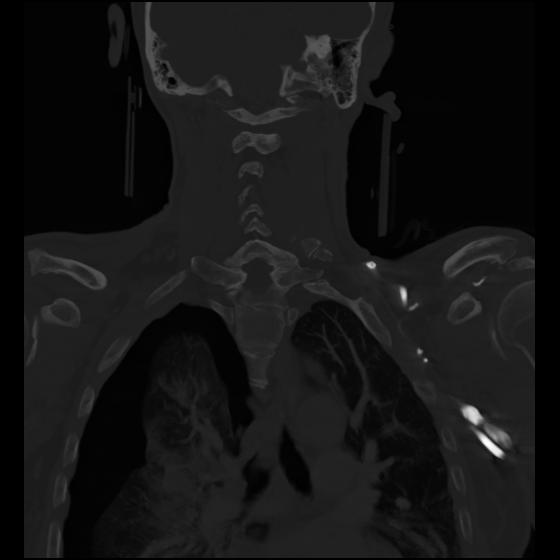

23 ANGIO,CE,Cor-MIP,5.000,ANGIO,Cor-MIP,